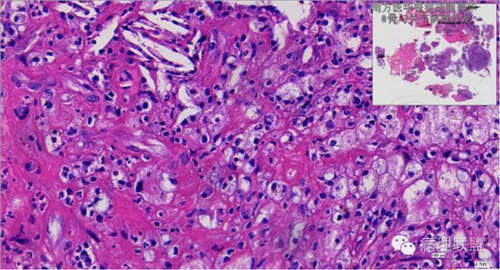

来源于组织细胞的相似性骨病ECD vs RDD 看图说话

病例由南方医华银病理魏建华提供,致谢。